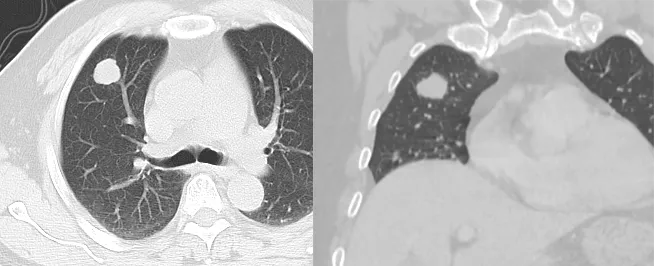

正常肺ct

Ct上这些征象与肺癌相似 上 中华医学网 131